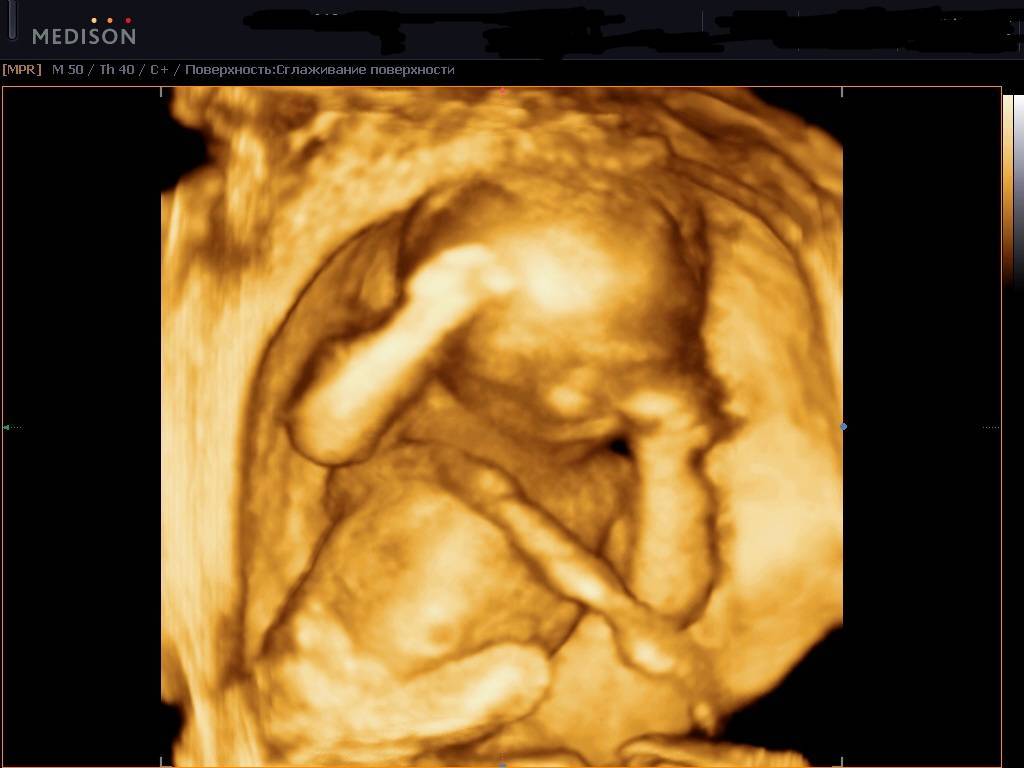

На 29 неделе беременности ваш ребенок активно развивается и растет. Вес плода на 29 неделе беременности может колебаться от 1,2 до 1,4 кг, а длина от головки до пятки приближается к 38-40 см. Теперь он или она начинает выглядеть, как маленький новорожденный.

Как уже было сказано, вес младенца сейчас составляет около 1300-1400 г, а его рост достигает 35-38 см. Ежедневно головной мозг воспринимает массу информации, ведь у крохи на этом этапе хорошо развиты все чувства (слух, зрение, вкус). При ярком свете малыш щурится, отворачивается, а громкие звуки заставляют его вздрагивать.

С каждым днем размеры плода увеличиваются, из-за чего места в животике становится все меньше. На этом сроке, как правило, малыши уже не переворачиваются в утробе, а их движения становятся более осознанными. В большинстве случаев ребеночек занимает головное предлежание. Иногда кроха располагается ягодицами вниз и находится в такой позиции до самых родов (тазовое предлежание).

На 29 неделе беременности на головке у малыша уже видны волосики. Сейчас они напоминают скорее пушок. Вместе с этим, пушок, который присутствовал на теле (лануго), исчезает. Уменьшается также количество защитной смазки. С каждым днем увеличивается жировая прокладка и малыш все больше становится похожим на новорожденного. Кожа приобретает светло-розовый оттенок, появляются так называемые младенческие складочки и милая припухлость на щечках.

- Внешне ребенок практически не отличается от новорождённого, откладывается жирок, кожица распрямляется, просматриваются пухленькие щечки, растут кудри, при этом пушок на теле постепенно скатывается;